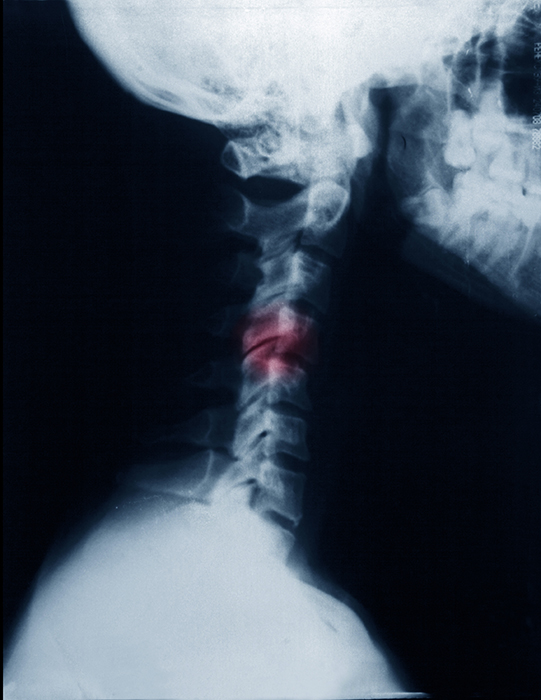

首にヘルニアがあり、痛みと痺れに悩んでいました。勉強など同じ姿勢が続いたり、ラグビーのプレー中に走ったりタックルしたりといった時が特に辛かったです。施術を受けだして、まずだんだんシビレが取れてきて、その次に痛みが取れてきました。そして、いまではすっかり良くなっています!

当院の患者さんでも、長年の首の痛みがつづき、

といった診断をうけ、場合によっては手術が必要なほどの重度な痛みやシビレに悩んでいた方も大勢います。

佐賀リカバリング整体院。私が整体を習い始めた頃、この名前を知らない人は、モグリと言われていたほど、この院の存在は、すでに全国的に有名でした。そして、指導者としてもヘルニアに関する知識、技術、経験、自信は、他のベテラン講師達を圧倒していました。

私は、10代の頃に負った椎間板ヘルニアの後遺症や、20代の頃に負った10トントラックによる交通事故の後遺症に苦しむという経験をしました。

病院で様々な治療を行っても中々回復せず、当時、両親とともに色んな情報を探している中で、ある整体技術に出会いました。その治療を受けることで、痛みは完治。